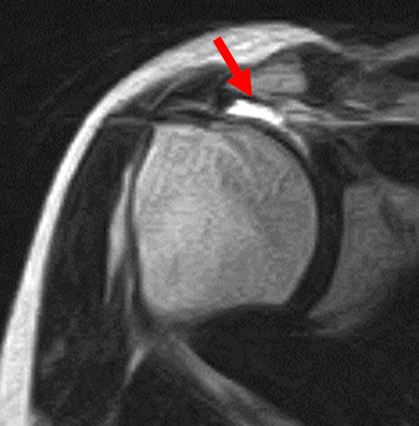

腱板断裂1

腱板断裂2

腱板断裂3